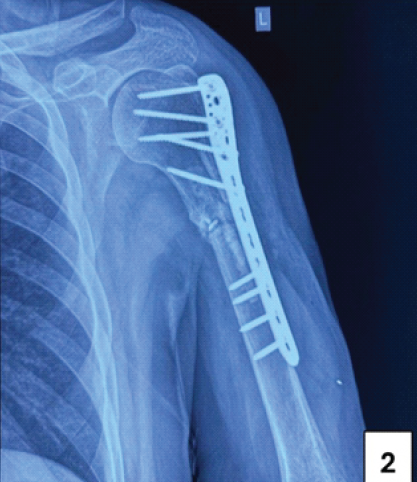

Postoperatively, the limb was immobilized with a universal shoulder immobilizer. There were no post-operative neurovascular deficits. The first post-operative dressing was performed on day 3, with suture removal on day 14. A staged rehabilitation program was initiated, beginning with passive pendulum exercises from the 3rd post-operative week onward. Assisted range of motion exercises were introduced from the 5th week, progressing to active range of motion exercises from the 9th week. At 6 months postoperatively, his shoulder range of motion included 110° of flexion, 30° of extension, 130° of abduction, 25° of adduction, 60° of internal rotation, and 35° of external rotation (Figs. 5, 6, 7, 8, 9, 10]. Elbow flexion was restored to 0–135°. Constant Shoulder Score improved to 80, indicating a good functional outcome. X-ray at 6 months showed a callus bridge across the non-union site (Fig. 2).

Figure 2: Post-operative 6-month follow-up X-ray.